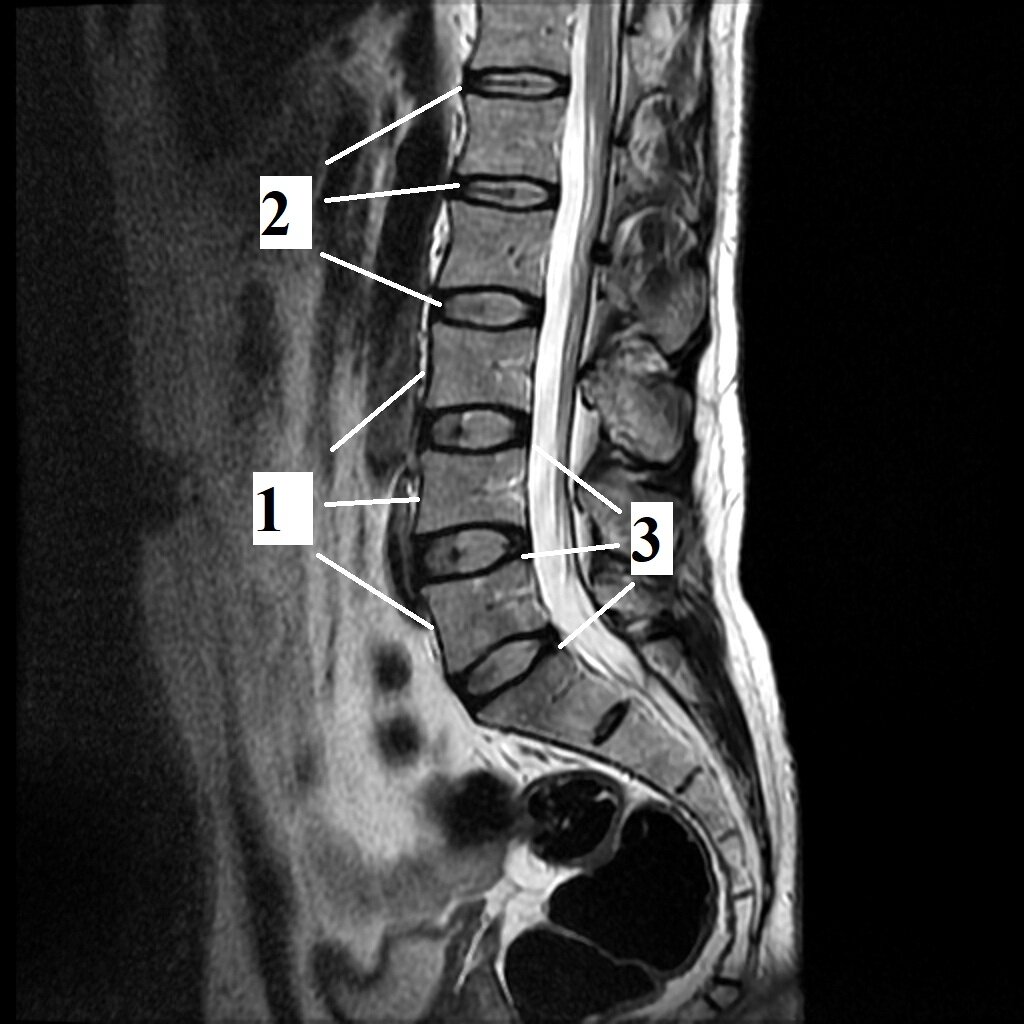

Изображение 1. Поясничный отдел позвоночника МРТ (норма). 1. Тела позвонков четкие и ровные, 2. Высота межпозвонковых дисков равномерная. 3 Межпозвонковые диска по задней поверхности не распространяются за границы тел позвонков.